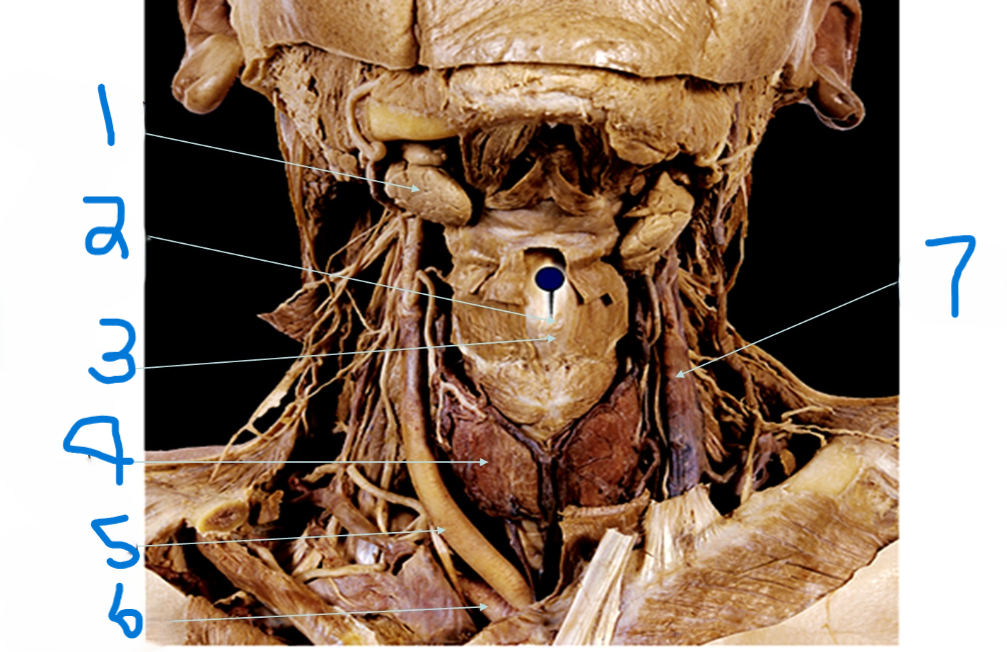

What is depicted by #1

Laryngeal Prominence (adams apple)

What is depicted by #2

Thyroid cartilage

What is depicted by #3

Thyroid gland

What is depicted by #4

Right common carotid artery

What is depicted by #5

Right subclavia artery

What is depicted by #6

Left internal jugular vein

What is depicted by #7